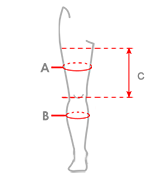

| Rozmiar | (A) Obwód uda 15 cm powyżej środka rzepki | (B) Obwód łydki 15 cm poniżej środka rzepki | (C) Odległość od szpary kolanowej do pachwiny | Sposób dokonywania pomiaru |

| S | min 44 cm – max 75 cm | min 34 cm – max 55 cm | min 21,5 cm |  |

| M | min 25,5 cm | |||

| L | min 28,5 cm |